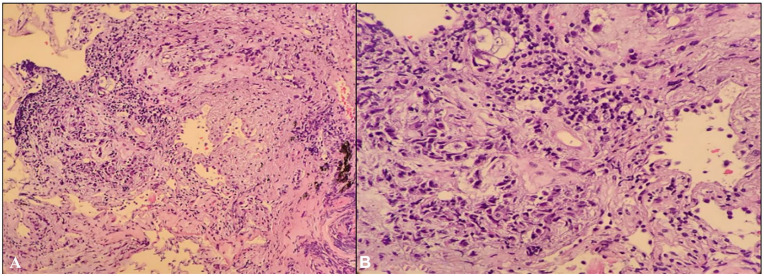

肺鳞状细胞癌(SCC)是非小细胞肺癌(NSCLC)的一种亚型,通常引起心包积液。10%至12%的肺癌病例有心包积液,但很少是最初的表现。我们报告一例68岁男性II型糖尿病合并慢性阻塞性肺疾病,表现为右上腹部疼痛、呼吸困难、厌食,怀疑肝胆疾病。影像显示有大量心包积液引起心包填塞。心包液细胞学检查确定为恶性肿瘤,随后胸部计算机断层扫描发现的肿块活检诊断为肺鳞状细胞癌。病人经历呼吸衰竭并伴有双侧气胸,导致决定开始安宁疗护。心包积液需要及时超声心动图和心包穿刺及细胞学检查。非小细胞肺癌相关积液表示IV期疾病,可通过免疫治疗和化疗姑息治疗。本病例强调了评估心包积液是否为恶性肿瘤的重要性,即使在表现不典型的情况下也是如此。我们提出一个恶性心包填塞被潜在的肝胆疾病所掩盖的病例。保持对恶性积液的高度怀疑是必不可少的,因为不这样做可能导致未确诊恶性肿瘤患者的发病率增加。

Squamous cell carcinoma (SCC) of the lung, a subtype of nonsmall cell lung cancer (NSCLC), uncommonly causes pericardial effusion. Pericardial effusions occur in 10% to 12% of lung cancer cases but are rarely the initial presentation. We report a case of a 68-year-old male with type II diabetes mellitus and chronic obstructive pulmonary disease who presented with right upper quadrant pain, dyspnea, and anorexia, suspicious of hepatobiliary disease. Imaging incidentally revealed a large pericardial effusion causing cardiac tamponade. Cytology of pericardial fluid identified malignancy, and biopsy of a mass found on subsequent chest computerized tomography diagnosed SCC of the lung. The patient experienced respiratory failure accompanied by bilateral pneumothorax, leading to the decision to initiate hospice care. Pericardial effusion warrants prompt echocardiography and pericardiocentesis with cytology. NSCLC-related effusions signify stage IV disease, managed palliatively with immunotherapy and chemotherapy. This case emphasizes the critical importance of evaluating pericardial effusions for malignancy, even in instances where the presentation may be atypical. We present a case of malignant cardiac tamponade that was obscured by underlying hepatobiliary disease. Maintaining a high level of suspicion for malignant effusions is essential, as failure to do so may lead to increased morbidity in patients with undiagnosed malignancies.